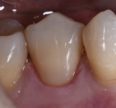

Crowns that blend perfectly into the adjacent teeth

#IPS #emaxMT on a root filled #10 Thanks Shin, as always, for your artistry. Clarrie #TheShinEffect